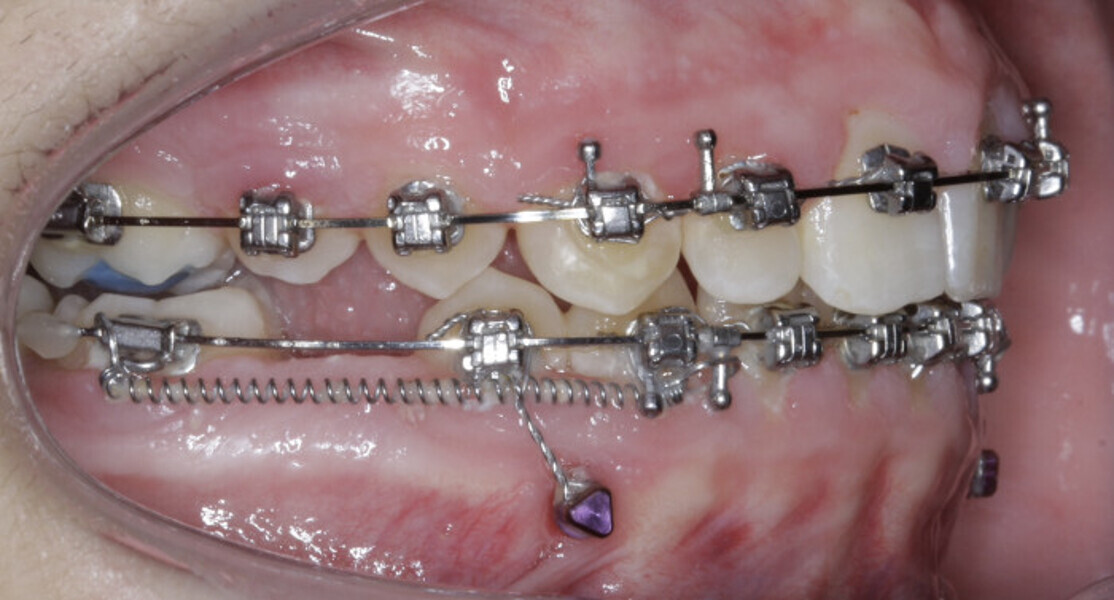

New Age orthodontics and orthopaedics with temporary anchorage devices